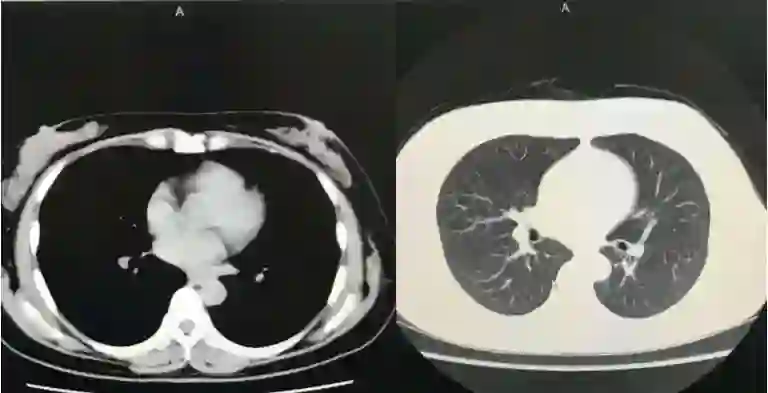

2011年11月CT复查结果

2017年11月CT复查结果